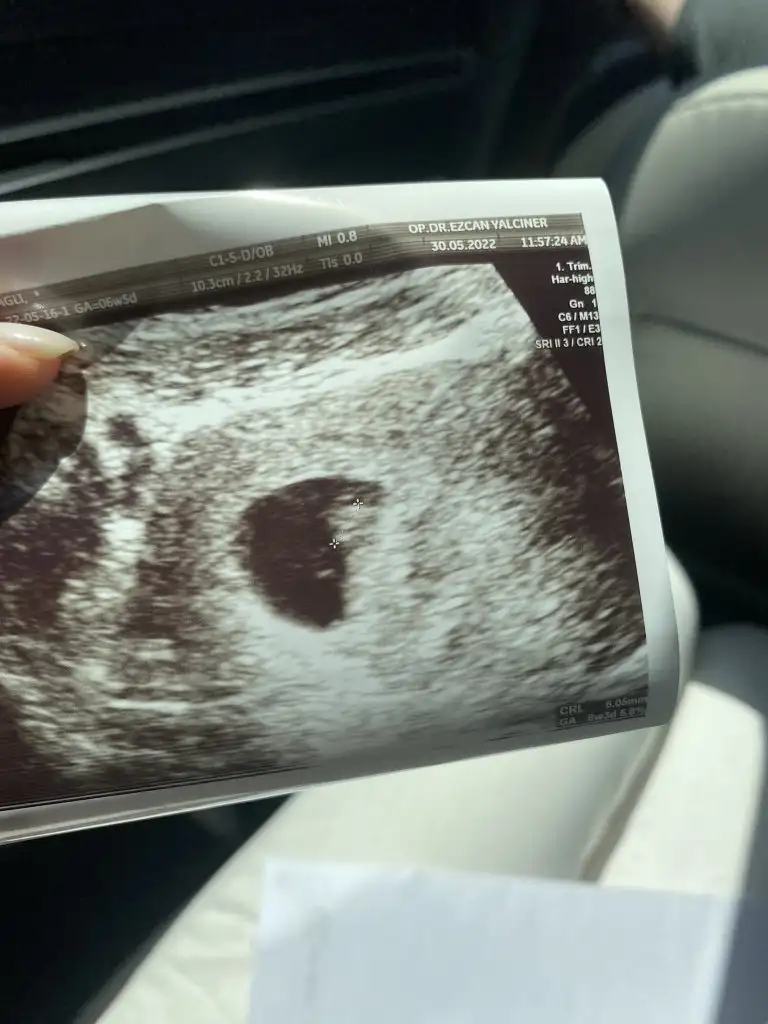

Merhaba, 5hafta 3 gunluk , karindan ultrasonla bakildi, cinsiyeti merak ediyorum , ilk goruntumuz buİlk ultrason resmine göre cinsiyet tahmini

Merhaba, 5hafta 3 gunluk , karindan ultrasonla bakildi, cinsiyeti merak ediyorum , ilk goruntumuz bu

Vajinal bakildi, cok tesekkür ederim